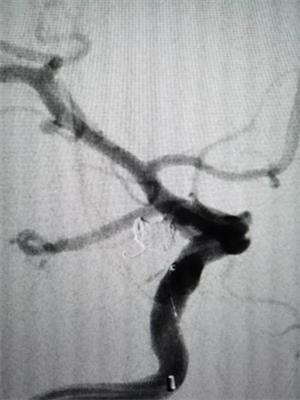

当天上午,64 岁的袁女士因突发剧烈头痛、呕吐急诊入院。CT显示蛛网膜下腔出血,进一步行头颈CTA检查确诊为颅内动脉瘤破裂。这是一种死亡率极高的疾病。神经内科介入团队在上级专家的指导下,迅速实施急诊栓塞手术,通过微导管将弹簧圈精准填入瘤体,成功栓塞破裂的动脉瘤。此类手术要求极高的精细度,术中需平衡栓塞效果与血管保护,我院团队的快速响应为患者赢得了生机。目前,袁女士神志清楚,病情稳定。

△图一:手术前可见后交通动脉瘤合并多个突起